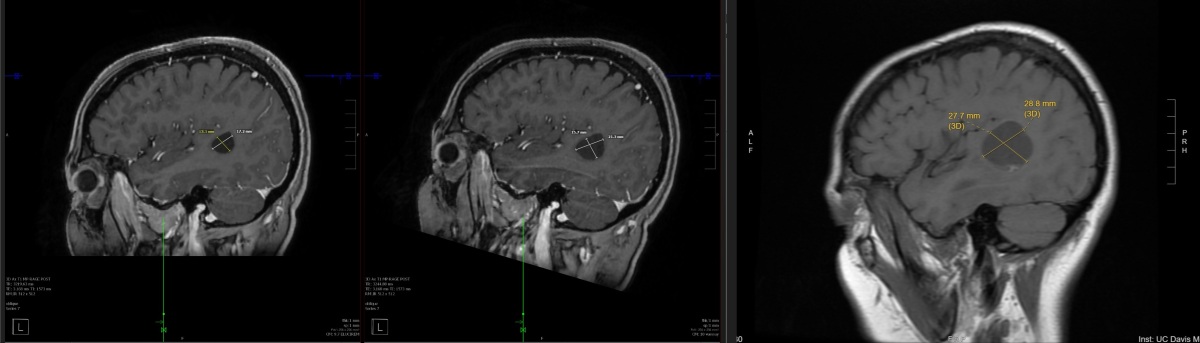

Progress Brain Scans - Right Lobe

From right to left, these images are of a spot of concern on my right anterior lobe that show the treatment effectiveness between the original scans in mid October, then the post treatment initiation scans from December and January. Initially, they wanted to drain and radiate these because of the size. My oncologist was pushing treatment first. I went with treatment first. And I'm glad I did because there's a strong possibility that I would be dead right now if I went the other way.